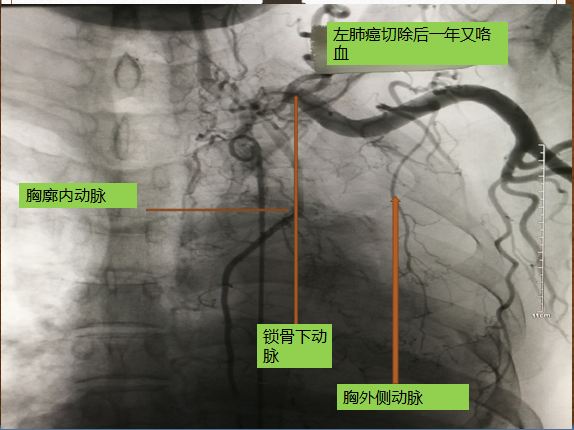

男性68岁,肺癌手术后咳血行介入治疗